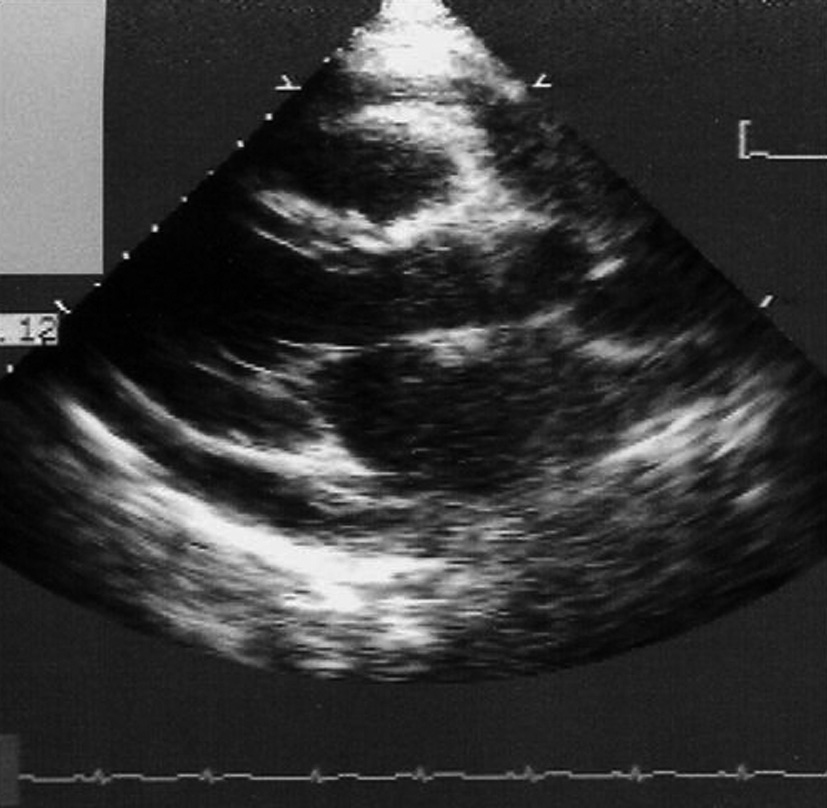

Epanchement péricardique : sur l’existence d’un simple décollement des deux feuillets péricardiques ou d’un épanchement péricardique qui apparaît sous la forme d’un espace clair vide d’écho (figure 1). L’échocardiographie apprécie l’abondance, la topographie et la tolérance hémodynamique de l’épanchement péricardique et confirme le diagnostic d’une éventuelle tamponnade.

Figure 1: Echographie d’une péricardite aiguë.